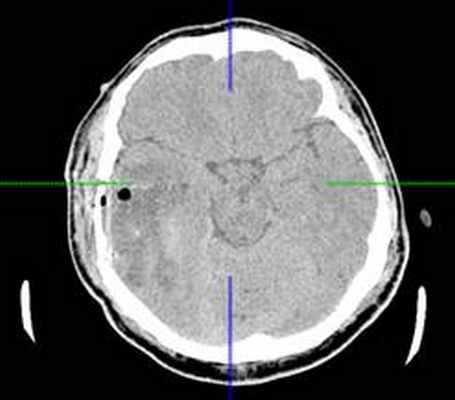

КТ головного мозга с контрастным усилением (24.03.2015): объемное кистозно-солидное образование правой теменно-височно-лобной области. Дислокационный синдром.